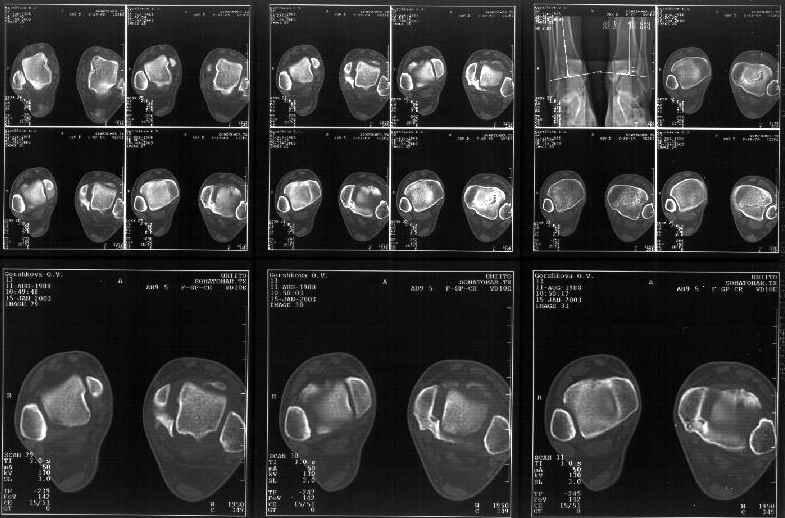

На следующий день пациентке сделали КТ. Может быть, после просмотра картинки будут другие предложения? Не убрать ли ве-таки этот фрагмент

позади внутренней лодыжки, который оттесняет таран кнаружи?

Думаю, КТ прочитан не верно. Задняя часть медиального маллеола, в сущности уже часть заднего маллеола стоит на месте и трогать её не следует. Передняя часть маллеола на 3-4 мм удалена от тарана. Сравните с пространством между

латеральным маллеолом и тараном. В норме все три должны быть одинаковы: между тараном и латеральным, задним и медиальным. Это главное условие устойчивого сидения тарана в голеностопном суставе.

Все-таки она как раз была была отколота и вместе с тараном смещена латерально.

Внутренняя лодыжка не была сломана, она как была на своем месте, так там и находится. Это таран от нее отдавлен кнаружи смщенным в его сторону фрагментом позади внутренней лодыжки. За счет чего и есть проявления нестабильности связок.

Мне в тоже время совершенно ясно видно по той же КТ, по 4 срезам, расположенным в центре и вверху пленки, что перелома внутренней лодыжки не было, в следующем собщении я приложу увеличенный фрагмент томограммы. А к этому письму прилагаю увеличеный фрагмент послеоперационной рентгенограммы, где выделил отколотый фрагмент

позади внутренней лодыжки. И он, как я вижу, находится между стержнем и тараном. А перелома внутренней лодыжки, и тем более смещения, IMHO

не определяется.

Отправитель: Alexander Chelnokov 12 Январь 2003, 14:55

Здесь 4 среза, начиная от основания лодыжки и проксимальнее. Где, по Вашему мнению, проходит линия перелома, отделяющая переднюю часть внутренней лодыжки от большеберцовой кости? Заранее спасибо.

Я пометил линию перелома черной линией.

К сожалению на последних присланных срезах КТ нет более низкого, через таран, среза, который был на прежнем майле. На XR я попытался показать

стержень внутри сустава и то как он раскрывает пространство между тараном и мед. малеолом.

Сегодня пациентке сделали сравнительную КТ. А ксиальные и Фронтальные срезы приложены. Ваше мнение?

Фронтальные

Аксиальные